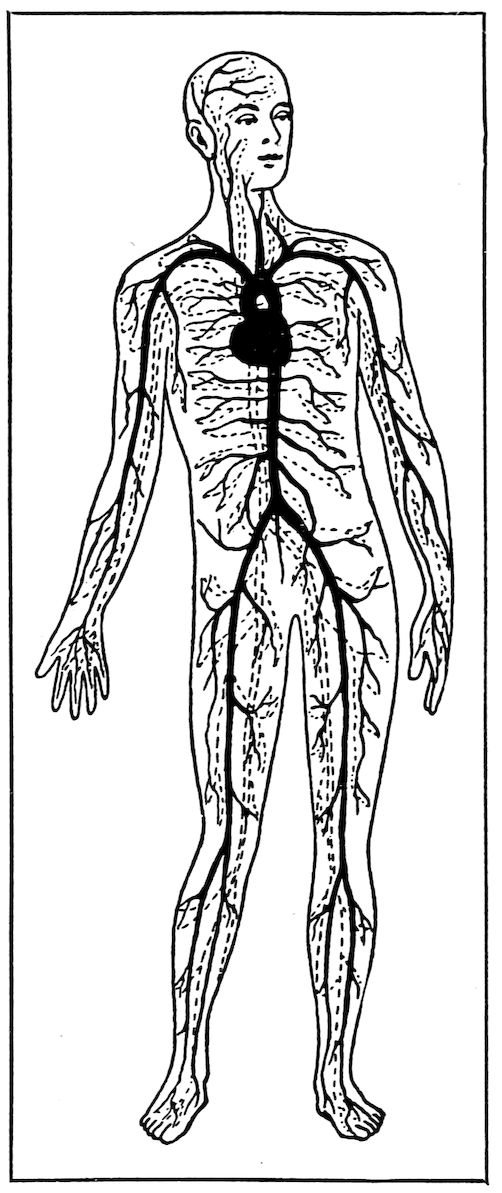

The Circulation of the Blood.

The blood is forced by the heart through the arteries (black lines), and returns to it through the veins (dotted lines).

The impure blood flows from the arteries into the veins through tiny canals. The veins are tubes something like the arteries, and they usually lie beside the arteries. They and the arteries are like the two tracks of a great railway line, one going from the main station, the heart, the other coming back.

But the blood in the veins is not like that in the arteries. Instead of being bright red, and healthy-looking, it is dark colored. It flows more slowly, and it is full of impurities 12which it is carrying away from the body. The veins carry this blood to the right side of the heart, and the heart sends it to the lungs. There are many blood vessels in the lungs, and they are divided into branches running in every direction through the lung tissue. When we draw in a deep breath, we fill the lungs with fresh air. This is at once taken up by the impure blood in the branching blood vessels. The impurities are breathed out with the air that leaves our lungs, and the blood once more becomes bright red and full of new life. In this way the blood is purified. Then it is sent back to the heart, all ready to start out again through the body. The whole journey is made every two minutes.